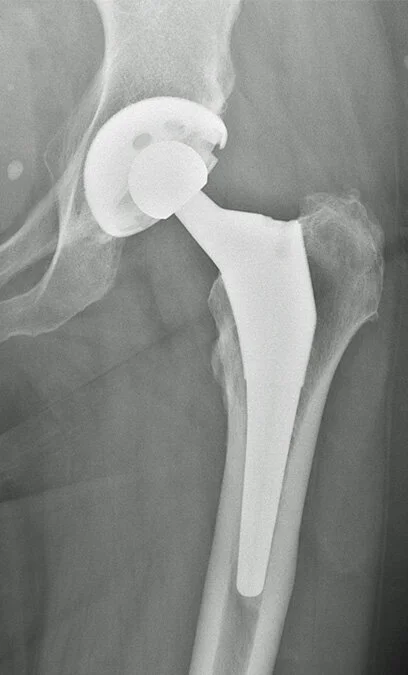

This 71 year old lady has osteoarthritis of the hip with protrusio (the femoral head has migrated toward the pelvis). Using the patient’s own femoral head as graft material, the centre of rotation, leg length and offset have been restored.

Metal on poly-ethylene bearing (Hybrid THR, Cemented Exeter stem with uncemented socket with screws)